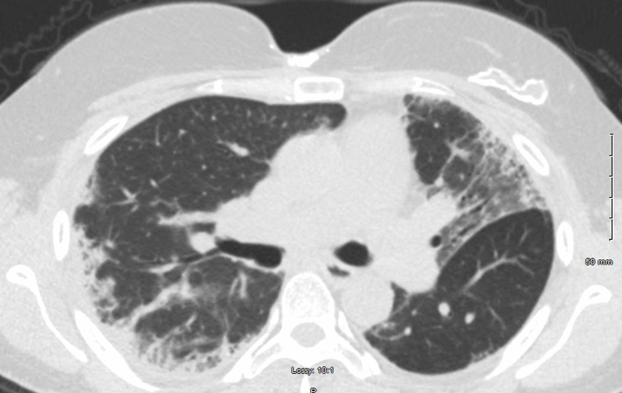

With regards to her pulmonary fibrosis, she was started on Nintedanib 150mg twice daily. Her dyspnea improved, and she was tapered down to 100 mg twice daily. Clinical improvement was mirrored by radiological improvement on computed tomography taken at diagnosis and two years later (Figures 2 and 3). She has been maintained on Mycophenolate 500 mg twice daily and Nintedanib 100mg twice daily for over two years without significant relapse. Malignancy screening including computed tomography of the chest, mammogram, pap smear, and colonoscopy were negative.

Figure 2: Computed tomography of the chest without contrast, taken upon diagnosis, indicating pulmonary fibrosis.